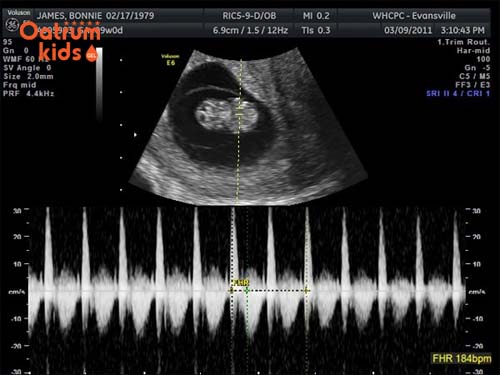

Không chỉ bé phát triển thay đổi mà mẹ cũng sẽ có những thay đổi nhất định theo từng giai đoạn của thai nhi. Khi thai nhi được 10 tuần tuổi thì mẹ đã có thể nghe rõ được nhịp tim của con thông qua các thiết bị siêu âm hiện đại.

Mẹ nên đi khám thai định kỳ để chắc chắn rằng bé yêu phát triển tốt, cần làm một số xét nghiệm quan trọng do bác sỹ chỉ định. Đặc biệt khi đi khám nên yêu cầu bác sỹ cho mẹ nghe rõ nhịp tim của thai nhi, đảm bảo trong ngưỡng 110-160nhịp/phút.